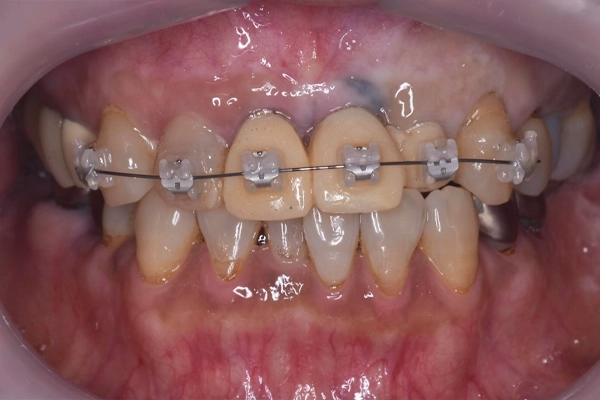

噛み合わせの状態

before

after

前歯の矯正治療

上顎と下顎の前歯の叢生(ガタガタした歯並び)の改善、左上2番の歯列改善のため右上3番〜左上3番、右下3番〜左下3番に唇側ブラケットを装着し歯列改善を行いました。

上顎はインプラントをアンカー(支点)として唇側傾斜、移動させ、下顎は右下1、2番と左下1、2番を中間地点くらいに移動させました。

矯正治療の様子

治療前の正面から見た様子です。

矯正後、歯の先端のラインを整えることができました。